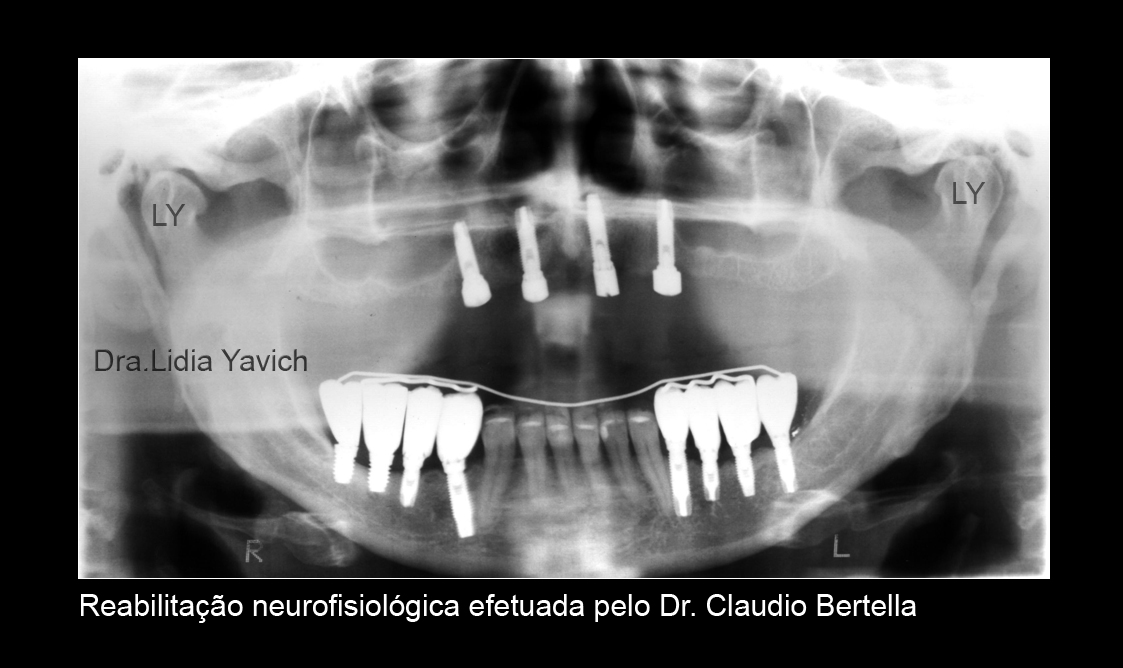

Terminado o tratamento de patologia da ATM encaminhei a paciente para o colega que fez a reabilitação neurofisiológica, mantendo a posição tridimensional obtida.

Os implantes tem mais de 5 anos de instalados.